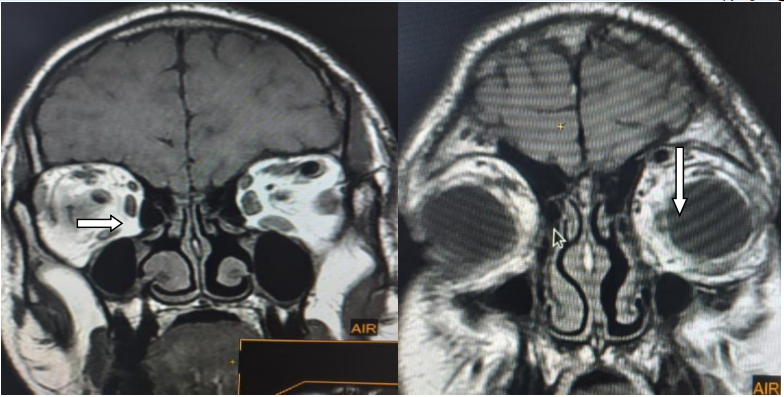

Figure 2: Coronal T1 and T1 + contrast magnetic resonance images of the orbit shows dilated left superior ophthalmic vein. Note the early contrast filling of the vein (arrow).

Figure 3: Coronal T1 magnetic resonance images show thickening of the left extra-ocular muscles (horizontal arrow) and oedema of the orbital soft tissues (vertical arrow) compared to the normal right side. Note also dilated left superior ophthalmic vein.